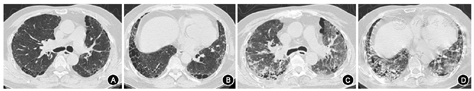

胸部X线检查可排除气胸或其他需要立即处理的胸部异常情况。胸部HRCT可准确显示肺实质异常的形态及部位,并可进一步对AE-IPF的影像学表现进行分类[9,31]。AE-IPF患者HRCT显示在典型UIP型[如网状影、牵拉性支气管和(或)细支气管扩张及蜂窝改变]的背景上,出现新的GGO和(或)实变影[9](图1)。AE-IPF患者胸部HRCT新增异常阴影可表现为3种类型:弥漫型、多灶型和周边型[31](图2)。

注:稳定期患者双肺外周分布的网格状、双下肺胸膜下蜂窝影,伴牵拉性支气管扩张(UIP型)(A、B);急性加重患者双肺在原有UIP型改变的背景上新出现弥漫性分布的GGO(C、D)。UIP为普通型间质性肺炎;GGO为磨玻璃影